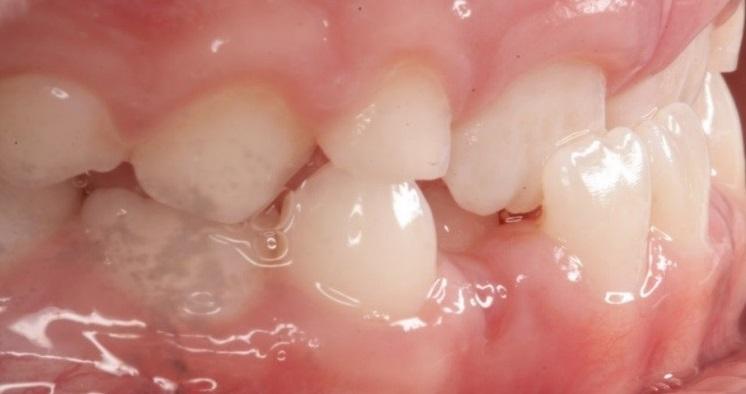

Incisor crossbite is when the upper front teeth (incisors) sit behind the lower front teeth.

Molar crossbite is when the upper teeth or jaw are narrower than the bottom teeth and when they bite down the top teeth sit down inside the bottom back teeth. This is particularly a problem if it causes the lower jaw to shift sideways when the teeth close together.